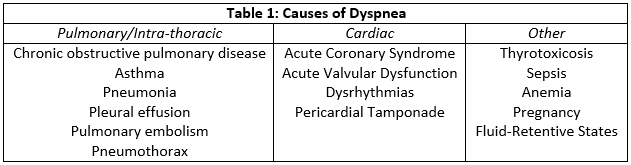

The biomarkers associated with heart failure are B-type natriuretic peptides (BNP) and N-terminal pro-B-type natriuretic (NT-proBNP) levels. BNP levels above 500 and NT-proBNP levels above 900 are highly associated with heart failure with the caveat that levels may not yet be elevated in the hyperacute phase.[5] Other causes of elevated natriuretic peptides include pulmonary hypertension, pulmonary embolism, renal failure, sepsis, and pneumonia. Cardiac biomarkers, including troponin T and I, may also be elevated in cases where acute coronary syndromes play a role in the development of heart failure. Further testing should be dictated by the patient’s history. Thyroid imbalance may precipitate atrial fibrillation or arrhythmia which may present as acute heart failure. The same is true of electrolyte or divalent imbalances. Other causes of shortness of breath should also be investigated (Table1). Finally, renal function impairment may lead to acute fluid retention and so blood urea nitrogen (BUN) and creatinine levels are examples of further testing that may be warranted.